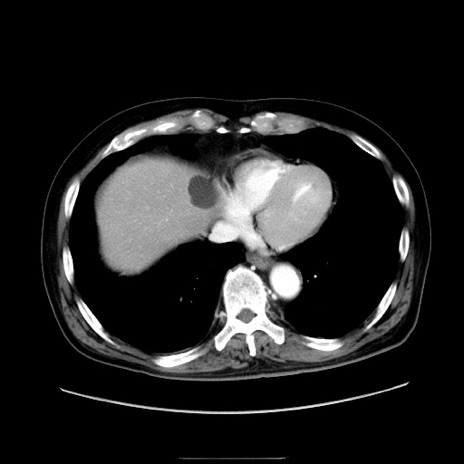

症例30(横断像)

【症例】80歳代男性

【主訴】臍周囲痛

【現病歴】約6時間前から臍下部痛が出現。次第に腹部膨隆・背部痛も生じてきたため来院。背部痛の場所は変化しない。

【身体所見】意識清明、BT 36.3℃、BP  131/87mmHg、P 87bpm、SpO2 100%(RA)、臍周囲自発痛・圧痛あり、反跳痛なし、自発痛部位に一致して板状硬あり、腹部膨隆、腸雑音減弱、CVA tenderness両側陰性。

【データ】WBC 19600、CRP 0.33